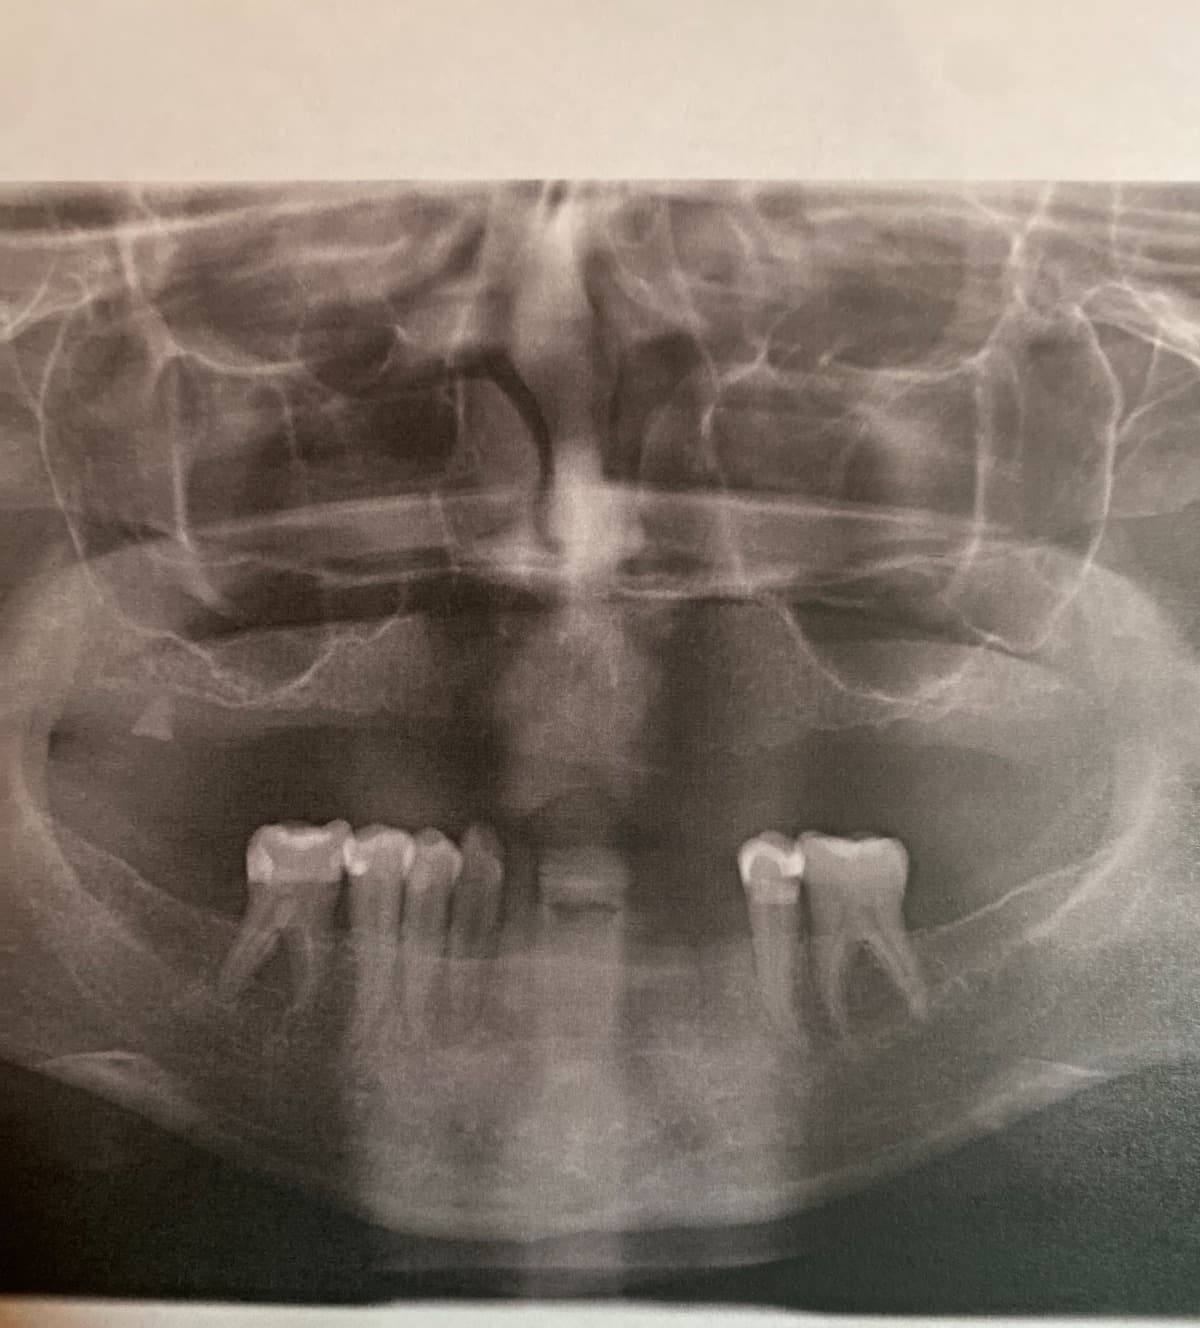

As some of you know my story, I have been dealing with issues with my teeth. I've been to many dentists all over the Midwest and have found one that will do the implant surgery that I need but I have to put a down payment down, which is at least 10 percent of the actual surgery cost. My dental insurance is only covering so much. I've been turn down from many loan companies and I am actively looking for a second job while also trying to work more hours at my current one. My plan was to go back to school to be able to enhance my career but I'm running out of time for the surgery because the bone on the top of my mouth is starting to deteriorate. If I wait too long, the bone will be gone and implants will no longer be an option for me.